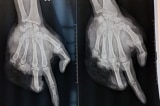

Bé trai 12 tuổi đứt ngón, dập nát bàn tay do nổ pháo tự chế

Sau tiếng nổ lớn, bé trai 12 tuổi bị đứt lìa ngón tay cái không thể hồi phục, ngón giữa bị đứt hai đốt, các ngón còn lại bị dập nát, gãy xương phức tạp.